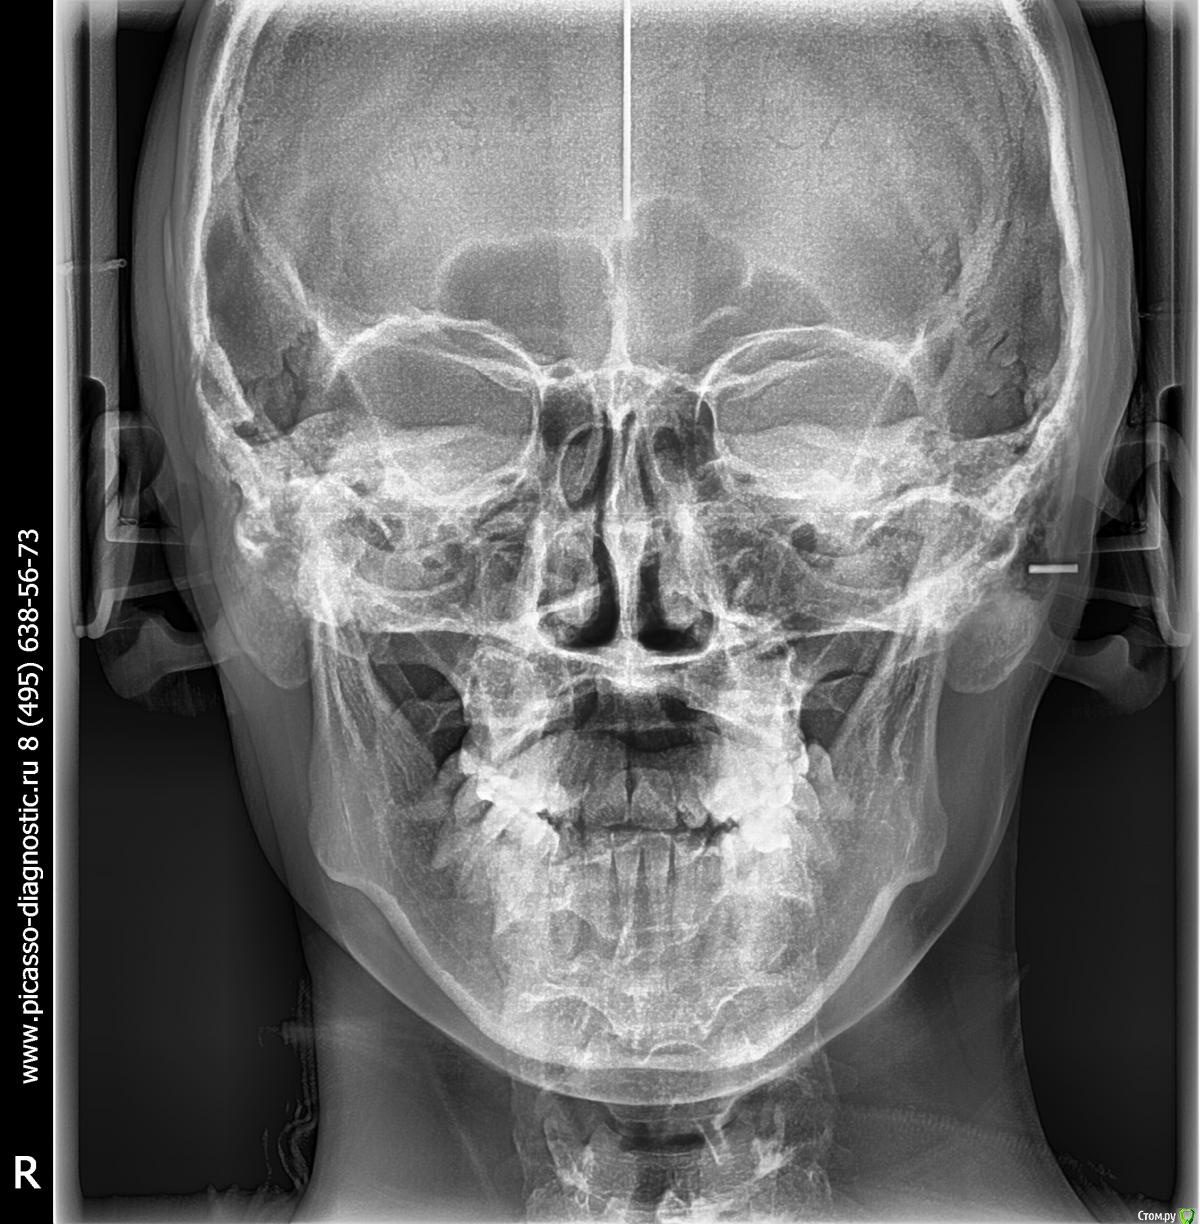

Led_9 Опубликовано 5 марта, 2015 Автор Поделиться Опубликовано 5 марта, 2015 Доброе утро! Спасибо за ответ. Снимки я не прикрепила специально, т.к. не хотела получить консультацию по плану лечения, а хотела получить совет именно на что следует обратить внимание при выборе доктора (вполне возможно что я зря засомневалась и такой подход абсолютно нормален). Но все же снимки прикрепляю. Ссылка на комментарий